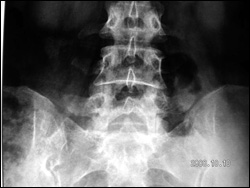

Diam Clinical Photo Dynamic Stabilisation- Interspinous Using DIAM Medtronic

This elderly lady was unable to stand, or walk due to incapacitating back pain. She had degenerative disorder of the lumbar discs leading to retrolisthesis and diminished disc space along with interspinous laxity and instability. She underwent an interspinous dynamic stabilization with DIAM at L4 and L5 interspinous area. This is a synthetic flexible implant (Medtronic Inc.) that allows a dynamic stabilization of the interspinous area in such cases and a symptom free life. Interbody fusion and pedicular fixation need not be done in such cases as these are essentially non dynamic fixations. She was pain free with no gait abnormality.